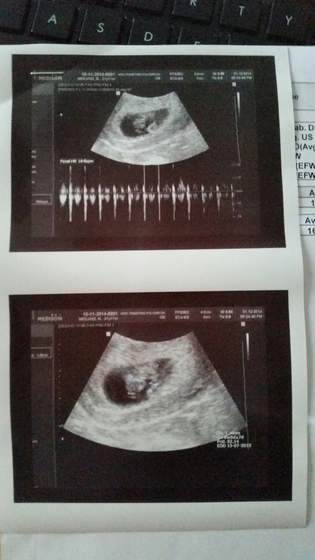

Wczoraj mieliśmy wizytę :-) Widziałam 1,81 cm maluszka i nawet coś na kształt dwóch nóżek i rączek

Serducho pięknie biło... Z USG wyszło, że maluszek ma 8t2d, więc praktycznie idealnie. We wtorek mamy się umawiać na genetyczne w okresie między świętami a nowym rokiem. Musimy niestety czekać, czy pani doktor którą chcemy będzie wtedy przyjmować.